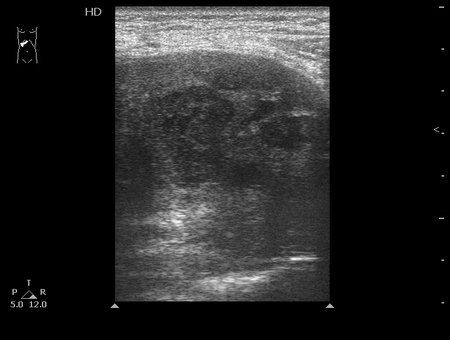

Типичная картина ##1-4:

Гипоэхогенное неоднородное округлое образование, окруженное эхогенным "демаркационным валом"

измененной паренхимы печени.

08-09-04-134127_KRAYNOVA_20.jpg